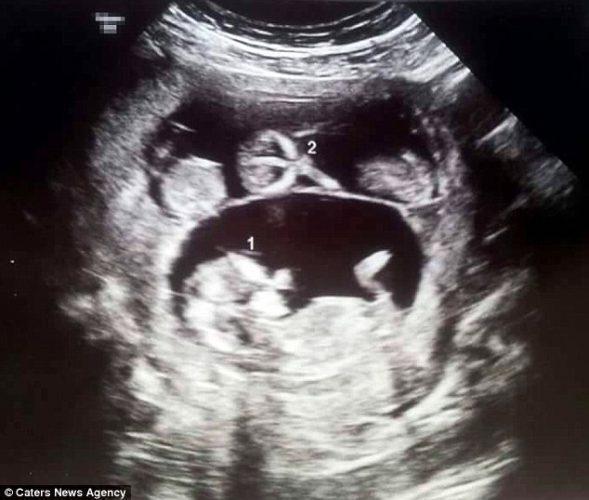

Uma vez que ela decidiu dar o mergulho, ela contou para sua família e voou para Los Angeles para ter o embrião implantado em uma clínica especializada. Como a gravidez progrediu, Shaniece notou que sua barriga era muito grande e, quando Joanna e Steve assistiram ao primeiro ultra-som de Shaniece, descobriram que estavam tendo gêmeos!

Durante uma varredura de 10 semanas, houve outra coisa… um terceiro bebê! Sim, Joanna e Steve iam ter trigêmeos. Surpreendente.